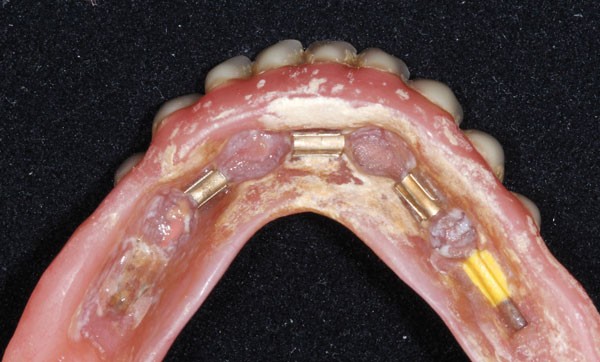

Dans cet article, les étapes de la réfection d’une prothèse amovible complète (PAC) maxillaire associée à une PACIR mandibulaire seront détaillées.

Le recours à des implants comme moyen de rétention secondaire des PAC peut se faire de deux façons :

– les prothèses sont retenues par des attachements axiaux (système Locator, système Novaloc, télescopes…) [4-6] ;

– elles sont retenues par des barres de conjonction reliant les implants entre eux [7,8].

Dans les deux cas, des parties mâles et femelles réparties entre les implants et l’intrados prothétique sont associées.